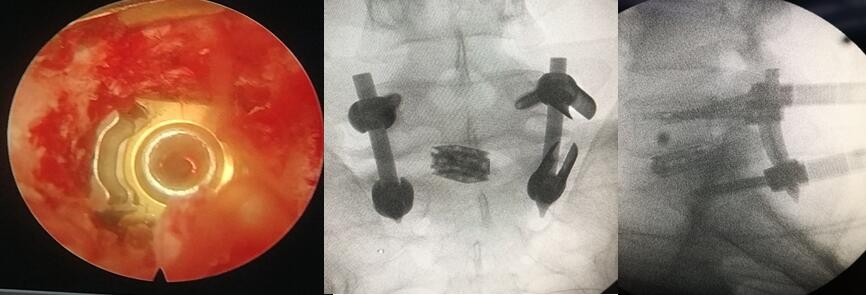

圖2:術(shù)中內(nèi)鏡下的術(shù)野和透視圖像

該患者腰痛伴左下肢疼痛麻木多年,嚴(yán)重影響正常工作及生活,輾轉(zhuǎn)多家醫(yī)院治療效果不佳。考慮患者過度肥胖,腰椎間盤突出伴鈣化、終板炎等因素,袁峰教授帶領(lǐng)脊柱外科微創(chuàng)團隊孫瑪驥、張新珠博士成功為患者實施了磁導(dǎo)航聯(lián)合全可視內(nèi)鏡下的腰椎管減壓融合內(nèi)固定術(shù),以最小的創(chuàng)傷和精準(zhǔn)的導(dǎo)航輔助完成了腰椎管減壓、椎間盤切除、椎弓根釘置入,椎間植骨融合術(shù),患者術(shù)后即感覺癥狀明顯改善,術(shù)后第二天下地行走。